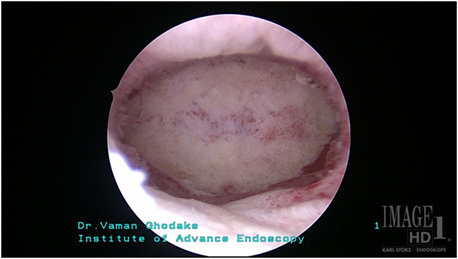

septate uterusafteroperation

ऑपरेशनंतर

3.गर्भाशय छोटे असणे

यामध्ये गर्भाशयाची पोकळी ही छोटी असते.ही पोकळी दुर्बिणीद्वारे ऑपरेशन करुन मोठी करण्यात येते.ह्या ऑपरेशनला ‘Metroplasty’ म्हणतात. घोडके हॉस्पिटलमध्ये Metroplasty शस्त्रक्रिया दुर्बिणीद्वारेच केली जाते.अशा प्रकारच्या ऑपरेशननंतर पेशंटना गर्भधारणा होण्यास मदत झाली आहे.